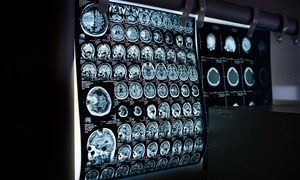

W badaniach przedklinicznych przeprowadzonych na modelach zwierzęcych wykazano, że implanty są w stanie autonomicznie dotrzeć do wskazanego obszaru mózgu i utrzymać tam stabilną pozycję. Mogą być także zasilane bezprzewodowo, co umożliwia ich aktywację i monitorowanie bez konieczności mechanicznego połączenia z zewnętrznym źródłem energii. Po implantacji urządzenia emitują impulsy elektryczne pozwalające modulować aktywność neuronalną w głębokich, trudno dostępnych regionach mózgu, bez zauważalnego wpływu na otaczające neurony. Obserwowano brak lokalnej reakcji zapalnej oraz minimalne zaburzenie mikrośrodowiska neuronalnego, co potwierdza bezpieczeństwo i potencjał długotrwałego użytkowania implantów. Technologia umożliwia także monitorowanie aktywności elektrycznej mózgu w czasie rzeczywistym, co stanowi istotną przewagę w kontekście badania mechanizmów chorób neurologicznych oraz oceny skuteczności terapii neuromodulacyjnej.

Implanty są wytwarzane przy użyciu technik mikroelektroniki kompatybilnych z procesami CMOS, co umożliwia produkcję w skali przemysłowej i zachowanie wysokiej precyzji konstrukcyjnej. Ich projekt uwzględnia możliwość integracji z naturalnymi naczyniami krwionośnymi i tkankami mózgowymi, co sprzyja precyzyjnemu ulokowaniu się w wyznaczonych miejscach. Urządzenia mogą być projektowane tak, aby modulować określone obszary neuronalne, dostarczać impulsy terapeutyczne, monitorować sygnały bioelektryczne lub zbierać dane diagnostyczne, co otwiera nowe możliwości w zakresie interfejsów mózg-komputer oraz spersonalizowanej terapii.

Technologia minimalnie inwazyjnych implantów stanowi alternatywę dla tradycyjnych metod chirurgicznych wymagających otwarcia czaszki, co zmniejsza ryzyko powikłań, obniża koszty leczenia oraz skraca czas rekonwalescencji pacjentów. Implanty typu „circulatronics” mogą w przyszłości zostać wykorzystane do terapii chorób neurodegeneracyjnych, padaczki, depresji lekoopornej, a także w monitorowaniu i wspomaganiu funkcji poznawczych. Wdrożenie tego typu urządzeń stwarza możliwość prowadzenia neuromodulacji w sposób precyzyjny, dostosowany do indywidualnych potrzeb pacjenta i w czasie rzeczywistym, co jest istotne w przypadku terapii wymagających regulacji sygnałów neuronalnych w konkretnych regionach mózgu.

Mimo obiecujących wyników badań na zwierzętach zastosowanie kliniczne wymaga jeszcze wielu etapów weryfikacji. Należy przeprowadzić badania nad długoterminową biokompatybilnością implantów, stabilnością ich położenia w tkance mózgowej, kontrolą zasilania i możliwości dezaktywacji urządzenia, a także wpływem długotrwałej neuromodulacji na funkcje poznawcze i zdrowie neuronalne. Dalszy rozwój technologii może umożliwić powstanie platform bioelektronicznych, które w sposób ciągły monitorują funkcje mózgu, wykrywają zaburzenia aktywności neuronalnej i dostarczają precyzyjnej, lokalnej terapii. W przyszłości wstrzykiwalne implanty mogą stać się alternatywą dla klasycznych interwencji neurochirurgicznych, zapewniając minimalny uraz tkankowy, elastyczność funkcjonalną i możliwość integracji z systemami monitoringu neurologicznego. Zastosowanie takich urządzeń może również stanowić fundament dla rozwiniętych interfejsów mózg-komputer, umożliwiając nowe sposoby diagnozy, terapii oraz wsparcia funkcji poznawczych.